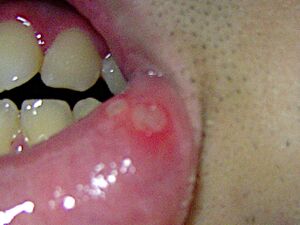

- Aphthous stomatitis is a condition where ulcers (canker sores) appear on the inside of the mouth, lips and on tongue. Most small canker sores disappear within 10–14 days. Canker sores are most common in young and middle aged individuals. Sometimes individuals with allergies are more prone to these sores. Besides an awkward sensation, these sores can also cause pain or tingling or a burning sensation. Unlike herpes sores, canker sores are always found inside the mouth and are usually less painful.[بحاجة لمصدر] Good oral hygiene does help but sometime one may have to use a topical corticosteroid.[28]